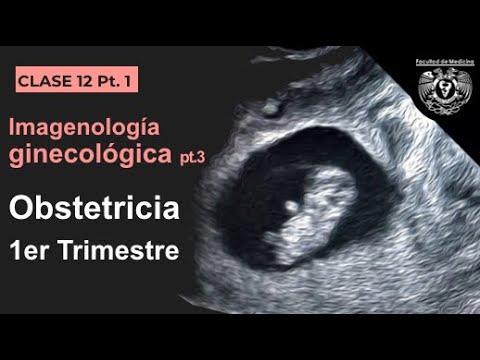

→ Realiza en la semana 7 de embarazo tu primera ecografía - El ultrasonido temprano es la mejor forma para confirmar el embarazo y comprobar la ubicación del embrión.

→ Realiza en la semana 7 de embarazo tu primera ecografía - El ultrasonido temprano es la mejor forma para confirmar el embarazo y comprobar la ubicación del embrión.